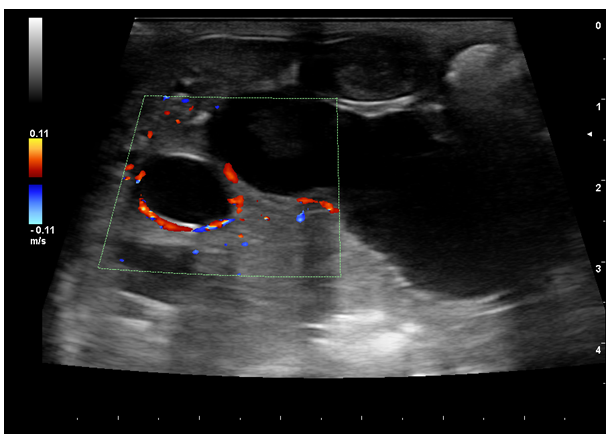

Increased dilatation of the intrahepatic bile ducts, with secondary compression of the local vasculature (A). Dependent echogenic debris is seen within the tubular bile ducts. Following the normal architecture of the bile ducts (localized in the proximity of the liver vasculature), the portal branches were difficult to visualize, causing the intraluminal portal vein sign16,27 (dilated ducts surrounding the portal vein) (Figure 3).

Figure 3 1-month follow-up ultrasound scan. Portal venous branches are partially surrounded by dilated bile - the intraluminal portal vein sign (red Doppler signal).

Symptomatic treatment and fluid therapy have been started, similar to the kitten from the same litter, with liver enzymes improving after 4 weeks. One month after starting the treatment, the second kitten started to gain weight compared with the sibling (3.7 kg, from 3.1 kg). 1-month post-treatment, blood results revealed a decrease in the liver enzymes (ALT 102 U/L, ALK=62 U/L). Treatment has been continued for another month; clinical signs have improved. As in the previous case, ultrasound examination follow-up highlighted transverse septae and echogenic to hyperechoic bile. The intraluminal portal vein sign (dilated ducts surrounding the portal vein) was noted as well during the ultrasound examinations and may represent a sign usually associated with bile duct ectasia, congenital or acquired.

In the present cases, advancement of the pathological process, intraductal bridging, echogenic septae formed by bile accumulation, gallbladder wall oedema, and thickening of the intrahepatic duct walls were seen during the ultrasonographic examination. The intraluminal portal vein sign16 (dilated ducts surrounding the portal vein) was noted during the ultrasound examinations.

Caroli's disease, or congenital intrahepatic bile duct ectasia, is a rare disorder in small animals. Differential diagnosis needs to be made primarily with single isolated choledochal cysts, polycystic liver disease, and biliary obstruction. Even though a biopsy is required to confirm the diagnosis, in cases when this cannot be achieved (clinically unstable patients or if the owners declined), the age of the patient and presentation can be supportive for a description of congenital malformations. Also, imaging findings like isolated cysts in other organs can help in the diagnosis. After the previous presentation of the patient, a sibling from the same litter was presented with the same clinical signs, imaging findings being similar, exception being made of the pancreatic cyst. This can prove the genetic relation in the transmission and the evolution of bile duct ectasia in cats. To the author's knowledge, this is the first case report description of a congenital intrahepatic bile duct ectasia coevolving with a pancreatic cyst in cats, with biliary tree changes seen in siblings from the same litter. In the presented cases, the intraluminal portal vein sign (dilated ducts surrounding the portal vein) was noted during the initial ultrasound examinations and may assist with the diagnosis.